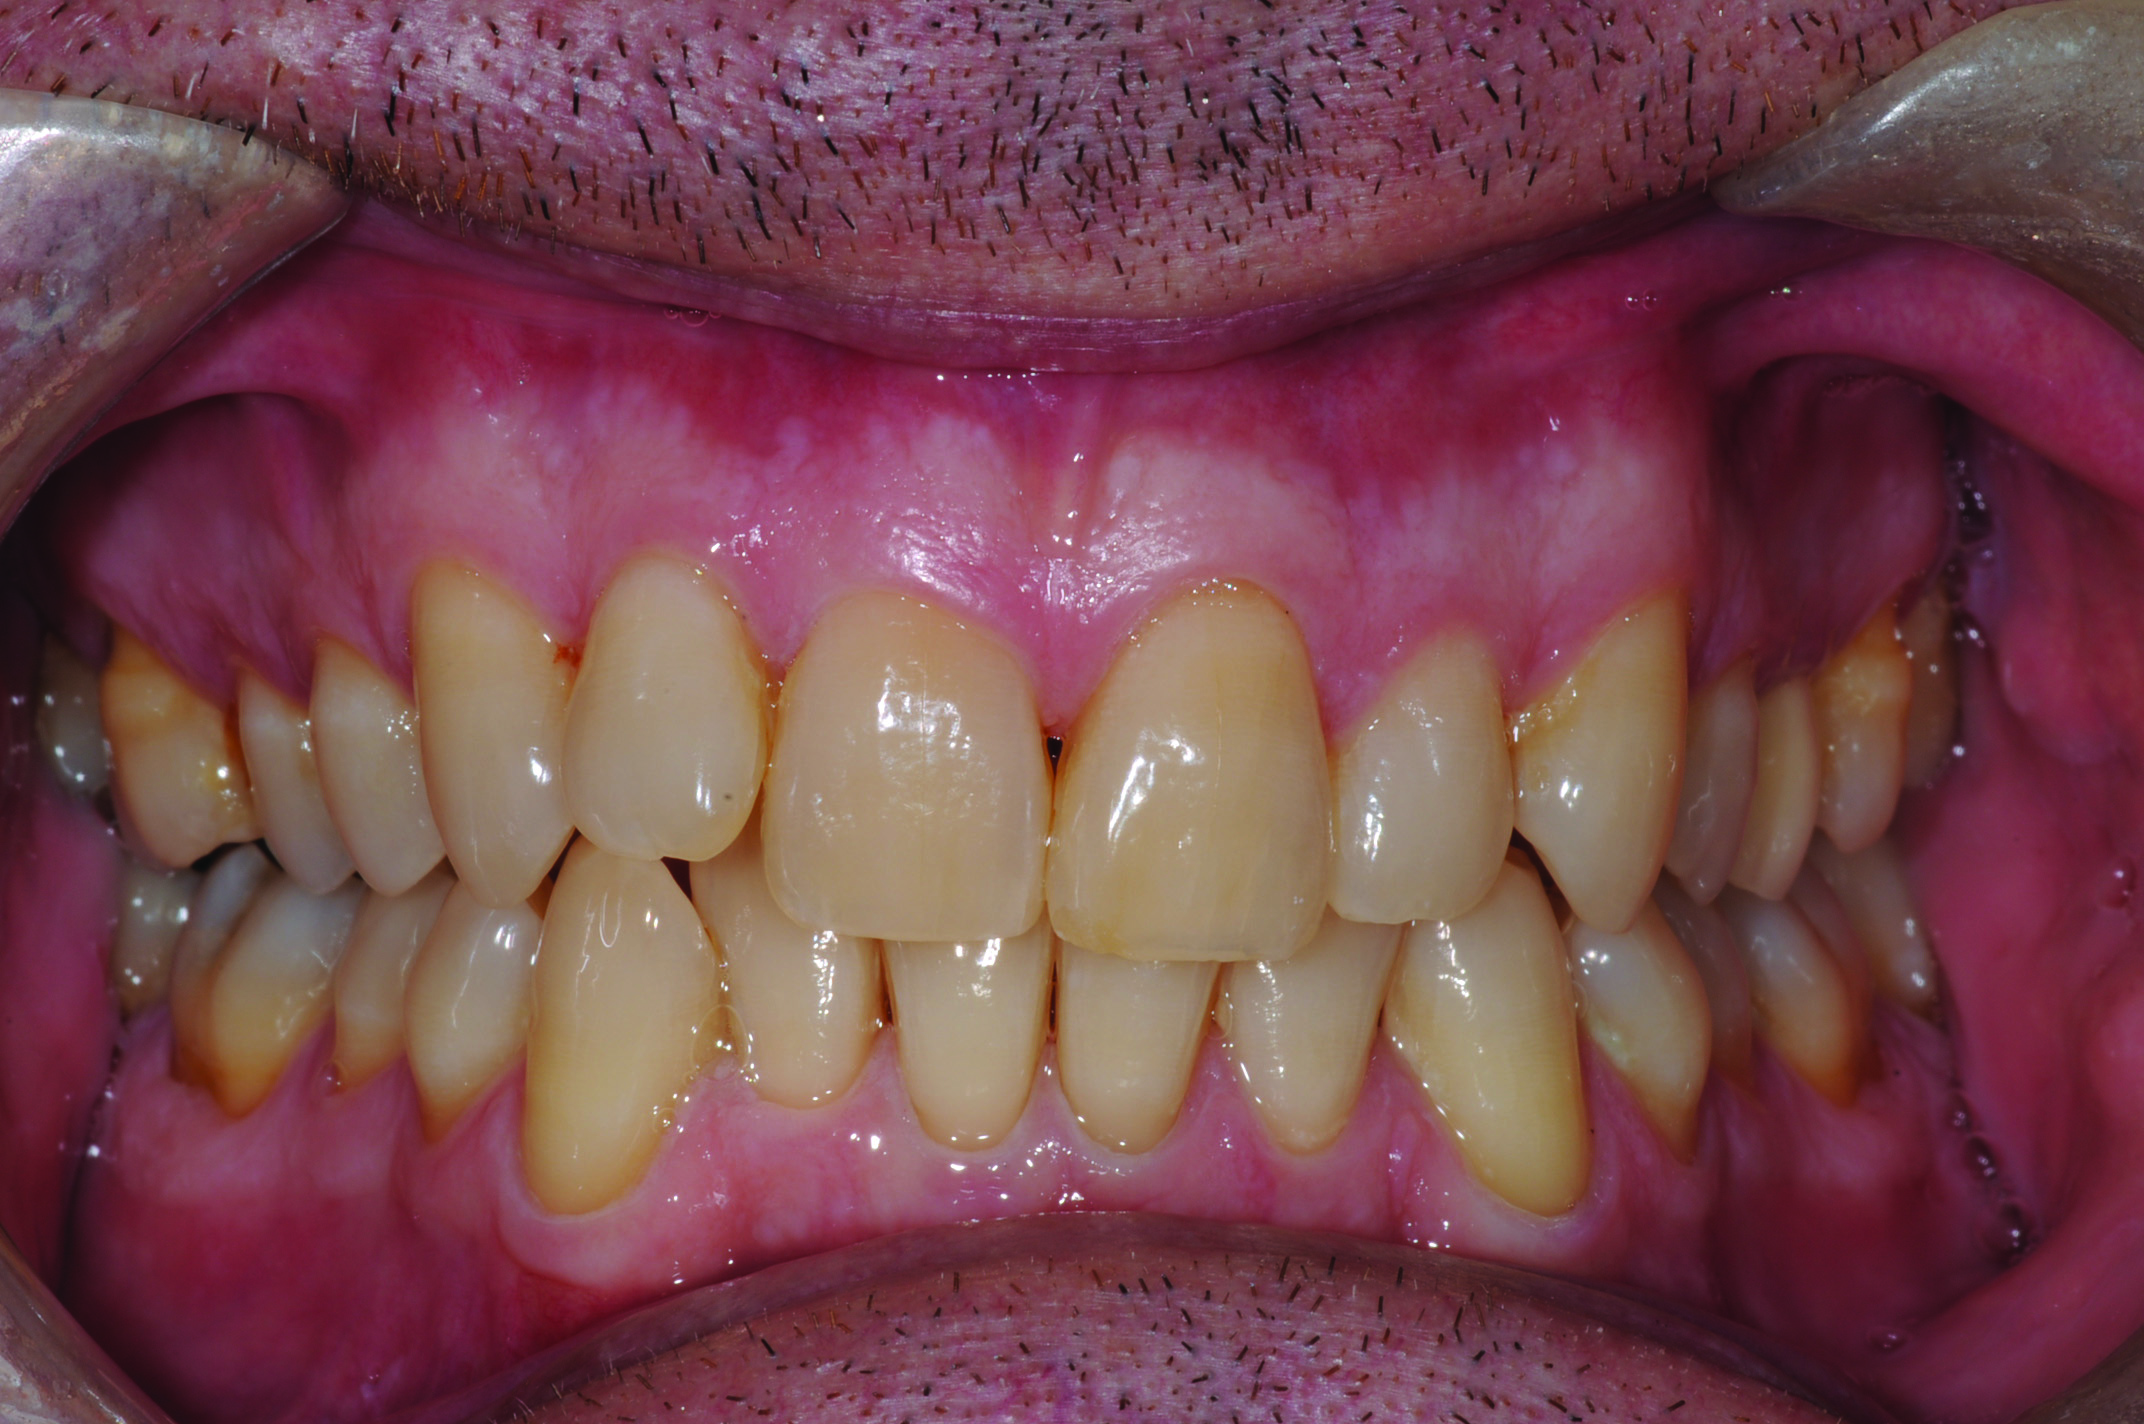

Fig 5. Development of dental side effects of MAD therapy. Photograph of female patient with teeth maximally intercuspated prior to treatment (AHI = 7.1 events/hr).

Figure 5

Fig 6. Photograph of teeth maximally intercuspated 1 year after patient began treatment with a MAD (Herbst appliance). With the jaw advanced 80% of maximum protrusion, the AHI was reduced to 1.4 events/hr. Compared to the pre-treatment occlusion (Figure 5), overbite and overjet had each decreased 2 mm.

Figure 6

In holding the jaw forward, MADs apply backward forces to the maxillary teeth and forward forces to the mandibular teeth in proportion to the amount of advancement. With time, these forces can produce changes in tooth or jaw position, resulting in changes in the dental occlusion.10,11 A decrease in overjet and overbite is most commonly observed (Figure 5 and Figure 6).